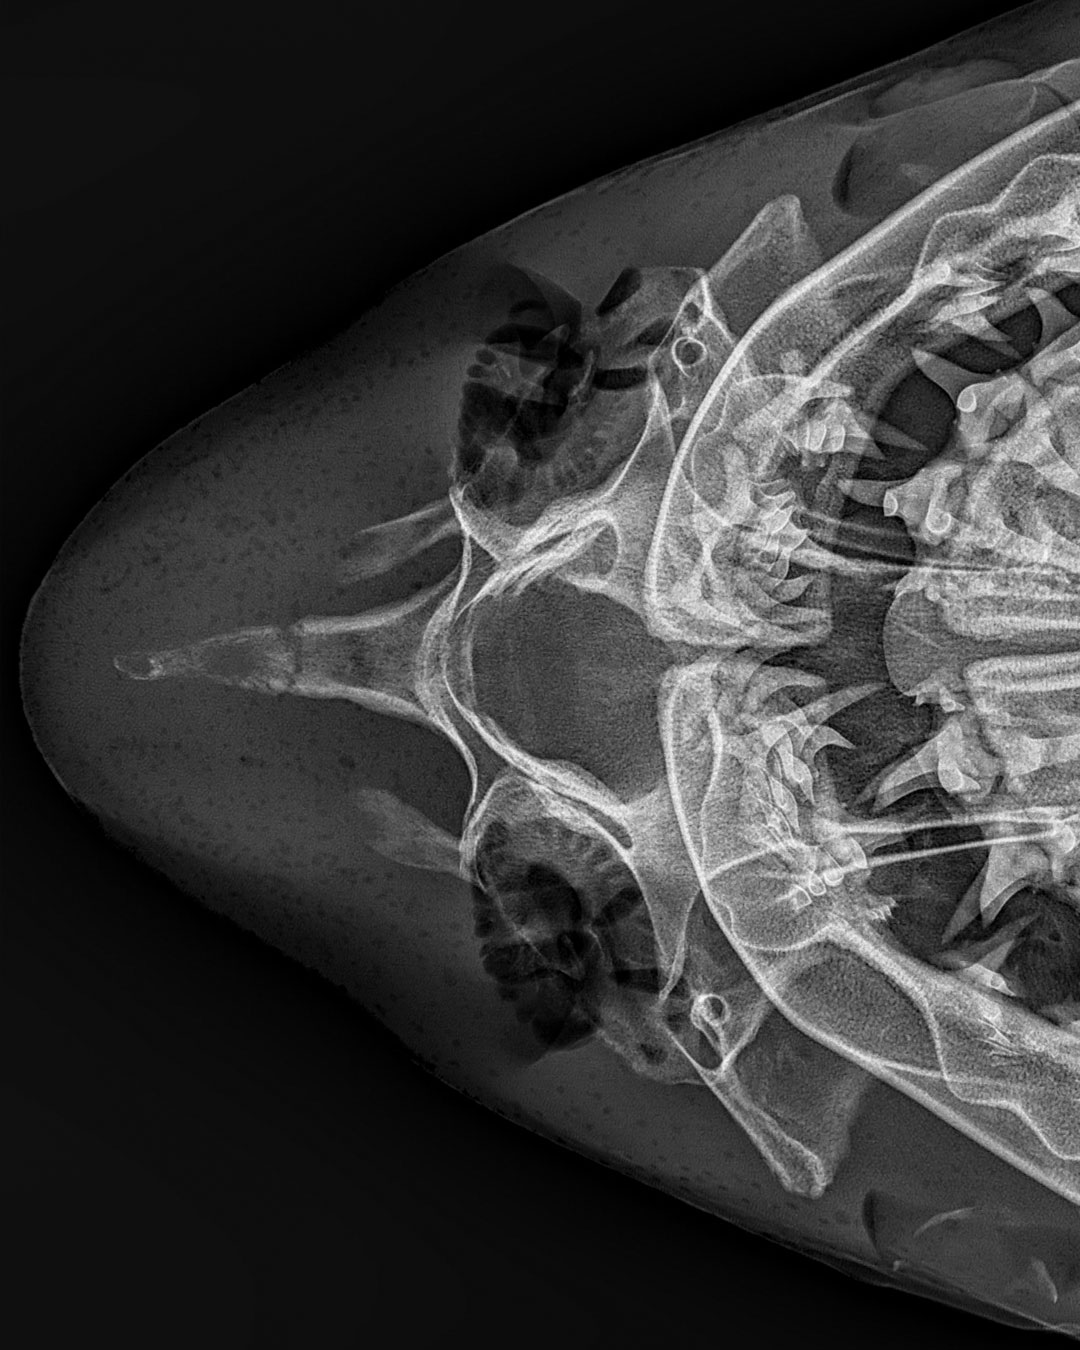

My, what pointy teeth you have! Sharks have skeletons made of cartilage, not bones, which is why their teeth often fall out. Download this spooky wallpaper at the link in our bio! 🦈